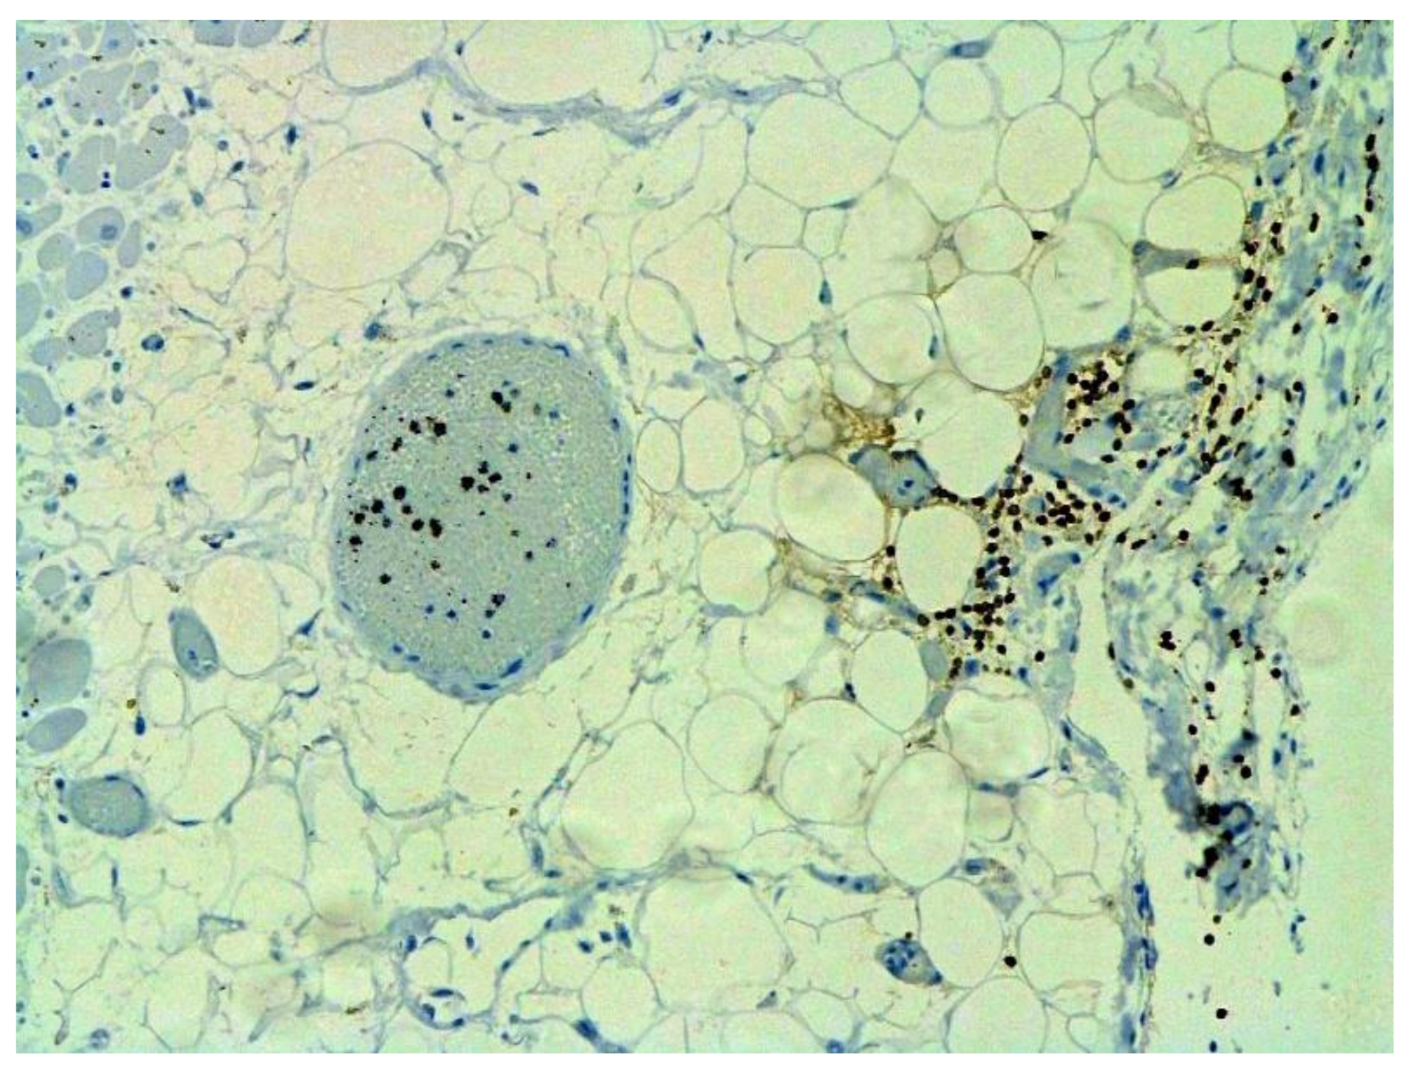

Figure 13.

Fibrosis in lung due to collagen 3. IHC ×200.

Figure 14.

Neoangiogenesis in lung by CD34+ cells. IHC ×200.

The dynamics of changes in ARDS associated with COVID-19 can only be judged by analogy with SARS and influenza A/H1N1pdm. In the late (productive) stage (after 7–8 days or more from the onset of the disease) of diffuse alveolar damage, macroscopically the lungs are enlarged, low-air, dense, fleshy, and can resemble the density of the liver, sometimes with diffuse whitish layers and areas of different sizes. Microscopically, siderophages, a relatively (in comparison with swine influenza) small number of hyaline membranes (Figure 9), fibrin, squamous metaplasia of the bronchial, and bronchiolar and alveolar epithelium can be detected in the lumens of the alveoli, respiratory and terminal bronchioles, the thickening of the interalveolar septa due to sclerosis, lymphoid (mostly CD3+ and CD 8+) (Figure 10 and Figure 11) and macrophage (Figure 12) infiltration, and the proliferation of type II alveolocytes. The nature of cytoproliferative changes of the epithelium in the trachea and bronchi remains unclear. In the final stage of the disease, sections of fibrous tissue may develop in all parts of the lungs (usually in the lower lobes) (Figure 13), which contributes to the development of chronic respiratory failure. It is notable that near the overgrowth of collagen fibers in the lungs, neoangiogenesis is also typical (Figure 14). The electron microscopic study revealed changed viral particles (Figure 15).